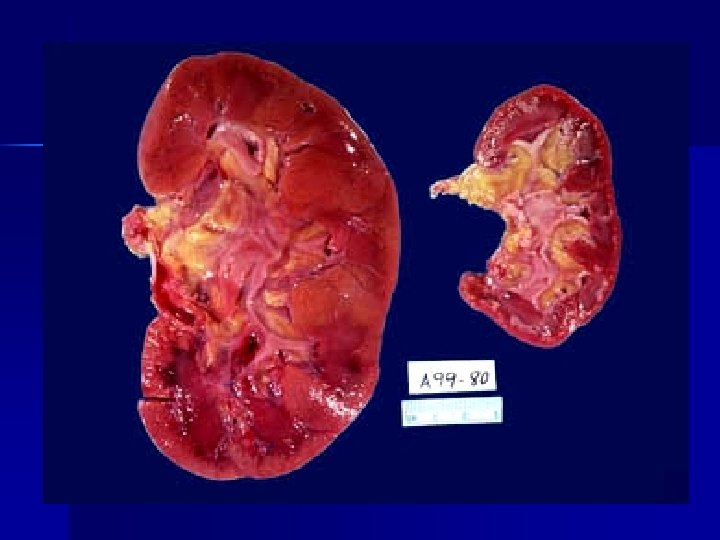

ATROFIA

Disminución del tamaño de células disminuye función de células-función del órgano. (estrés sostenido adaptación )

Causas: - Isquemia: Disminución de oxigeno, necrosis isquémica - infartos- oclusión vascular. - Inflamación crónica (infecciones virales o bacterianas) atrofia. - Disminución de la actividad del músculo esquelético: reposo prolongado, inanición o nutrición inadecuada. - Interrupción de las señales tróficas (denervación: polio) - Interrupción de las señales hormonales (ablación glandular)

- Demanda funcional aumentada. Músculos, hipertrofía cardiaca por hipertensión, hepatocitos (aumento de REL por estímulo de fenobarbital y drogas hipolipemiantes)- hepatomegalia fisiológica - Hipertrofia del riñón contralateral. - Más frecuentes en tejidos pemanentes y estables.